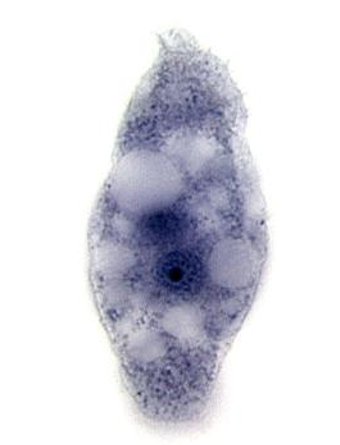

P. falciparum, gametocyte

7